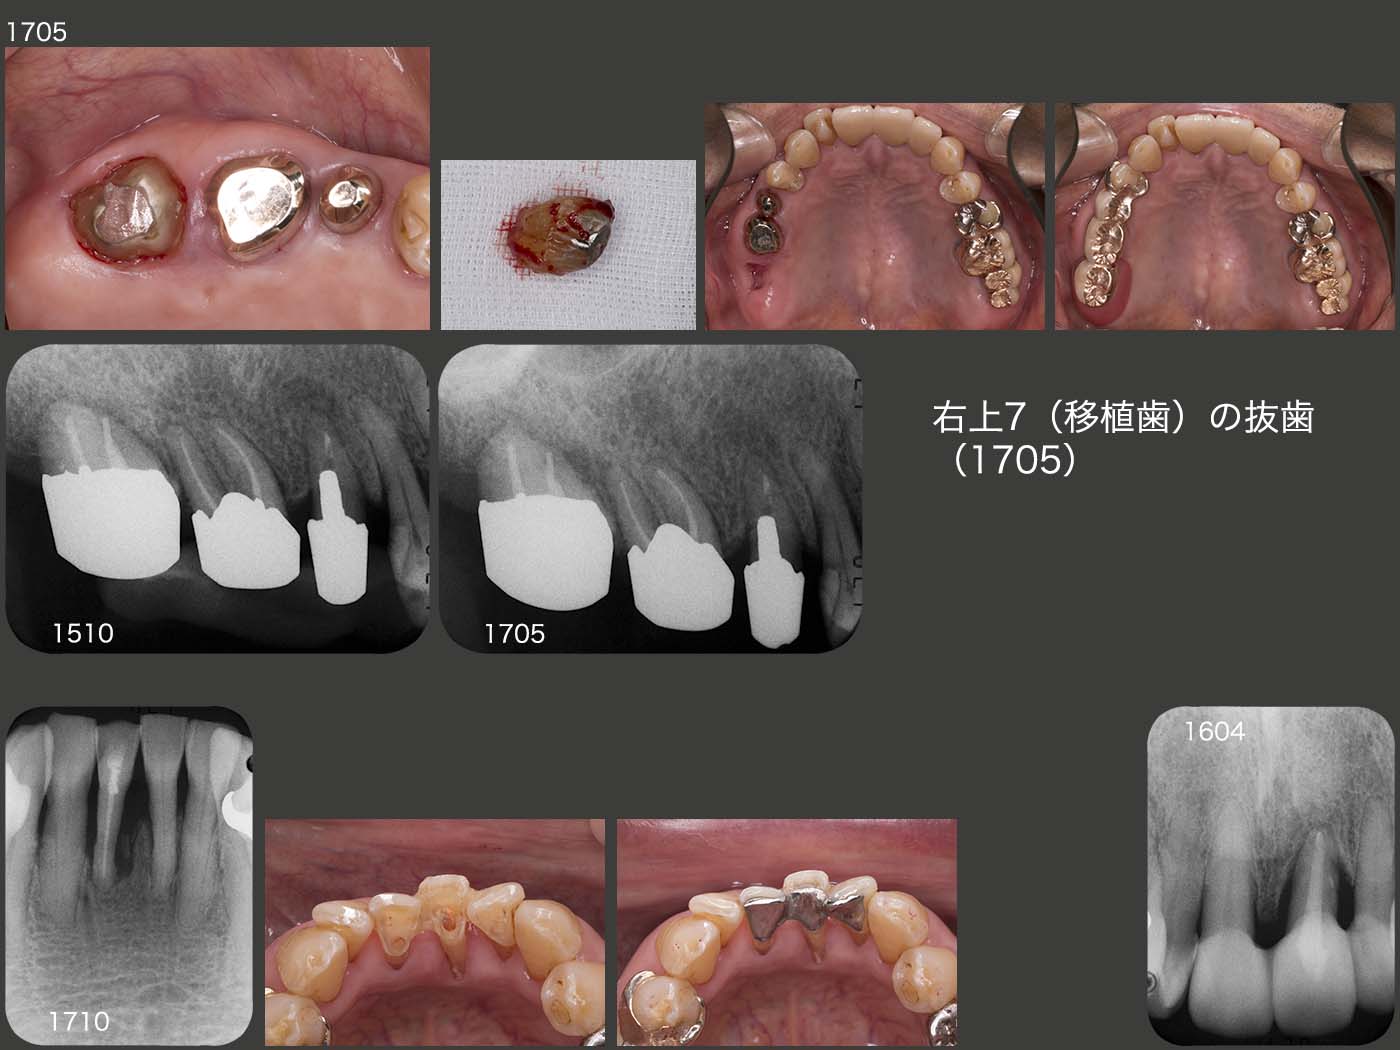

まず右上7(移植歯)に関しては,2016年12月の時点で歯周ポケットが遠心舌側に7mm認められた.17年5月には10mmになってしまったため,コーヌス内冠を外し,SRPを行うことにした.しかし,術中に歯が脱落してしまった.私の治療の拙さによることは間違いないが,それにしても大きなショックを受けた.一つ言い訳になるが,やはり,この歯が偏咀嚼主機能歯になってしまったことが早期脱落に影響を及ぼしているのではないかと考えている.

さらに右下1は,スライドにはないが16年4月にセメント質剝離を起こし,自発痛が生じたので抜髄した.また,17年7月にトウモロコシを食べたら歯がグラグラになってしまったとのこと.スーパーボンドで固定したが,またトウモロコシで外れてしまったため,今度は隣在歯と1次固定した.

左上1は歯周ポケットが最大8mm認められるが,特に変化がみられない.